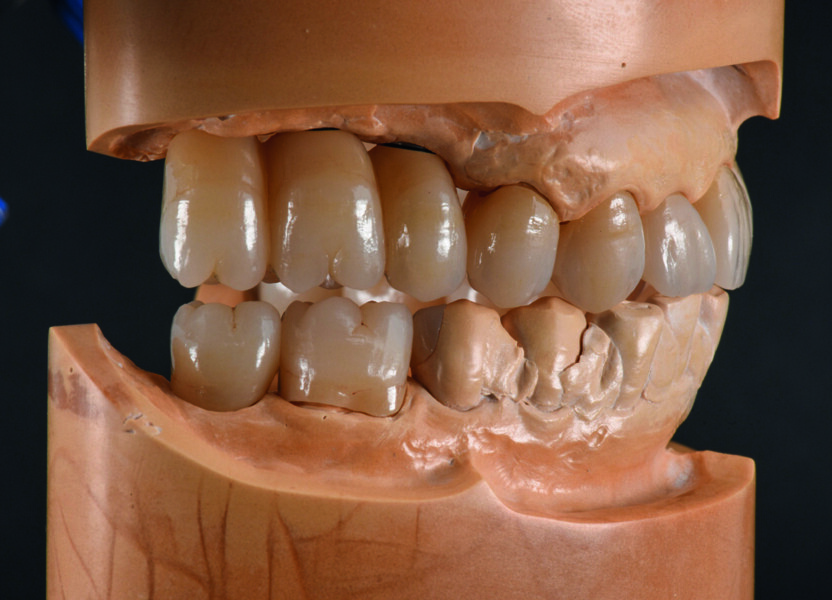

Enfin, je cherche à obtenir une pente canine sans contacts perturbants lors des mouvements de latérotrusion et de protrusion. Ces mouvements sont reproduits adéquatement et exactement, comme je les ai conçus dans l’articulateur Artex CR virtuel (Figs. 9a et b). Le flux de travail méthodique entre l’articulateur manuel et l’articulateur virtuel est tout simplement ingénieux, et simplifie mon travail quotidien. Néanmoins, cela ne fonctionne vraiment bien que si le fabricant coordonne l’articulateur et le système CAD/CAM, ce qui est le cas pour ces produits.

Fig. 9a : Surfaces occlusales et pente canine parfaites pendant le mouvement mandibulaire.

Fig. 9b : Surfaces occlusales et pente canine parfaites pendant le mouvement mandibulaire.